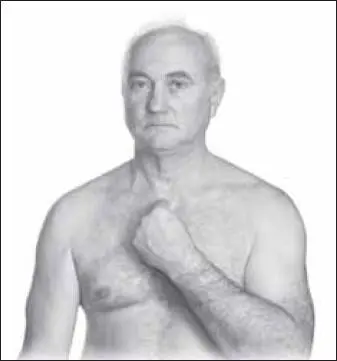

Начинаем с точки би-нао (расположена на месте прикрепления дельтовидной мышцы к плечу) (рис. 109).

Затем воздействуем на точку тянь-фу (расположена на передней поверхности плеча, на месте пересечения дельтовидной и двуглавой мышц) (рис. 110).